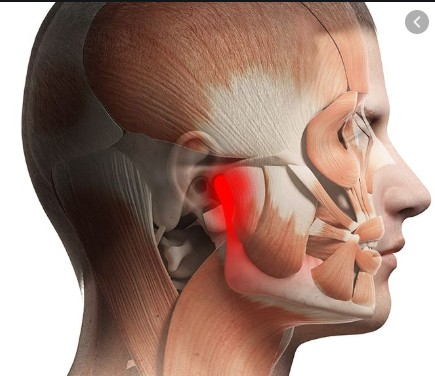

- Temperomandibular joint disorders are disorders that develop from

problems with the fit between the upper and lower teeth,

the Jaw Joint[TMJ]and the muscles in the face that control chewing and moving the jaw.

TMD can occur when your jaw opens, closes or moves from side to side

TMD pain can be experienced in the jaw joint as well as in the muscles of the face that control your jaw's movement

Symptoms include pain, clicking of jaw, inability to close or open jaw and headache that radiates to head and neck.

Type of Treatment are simple corrective splints , full mouth rehabilitation , joint lavage and surgery.